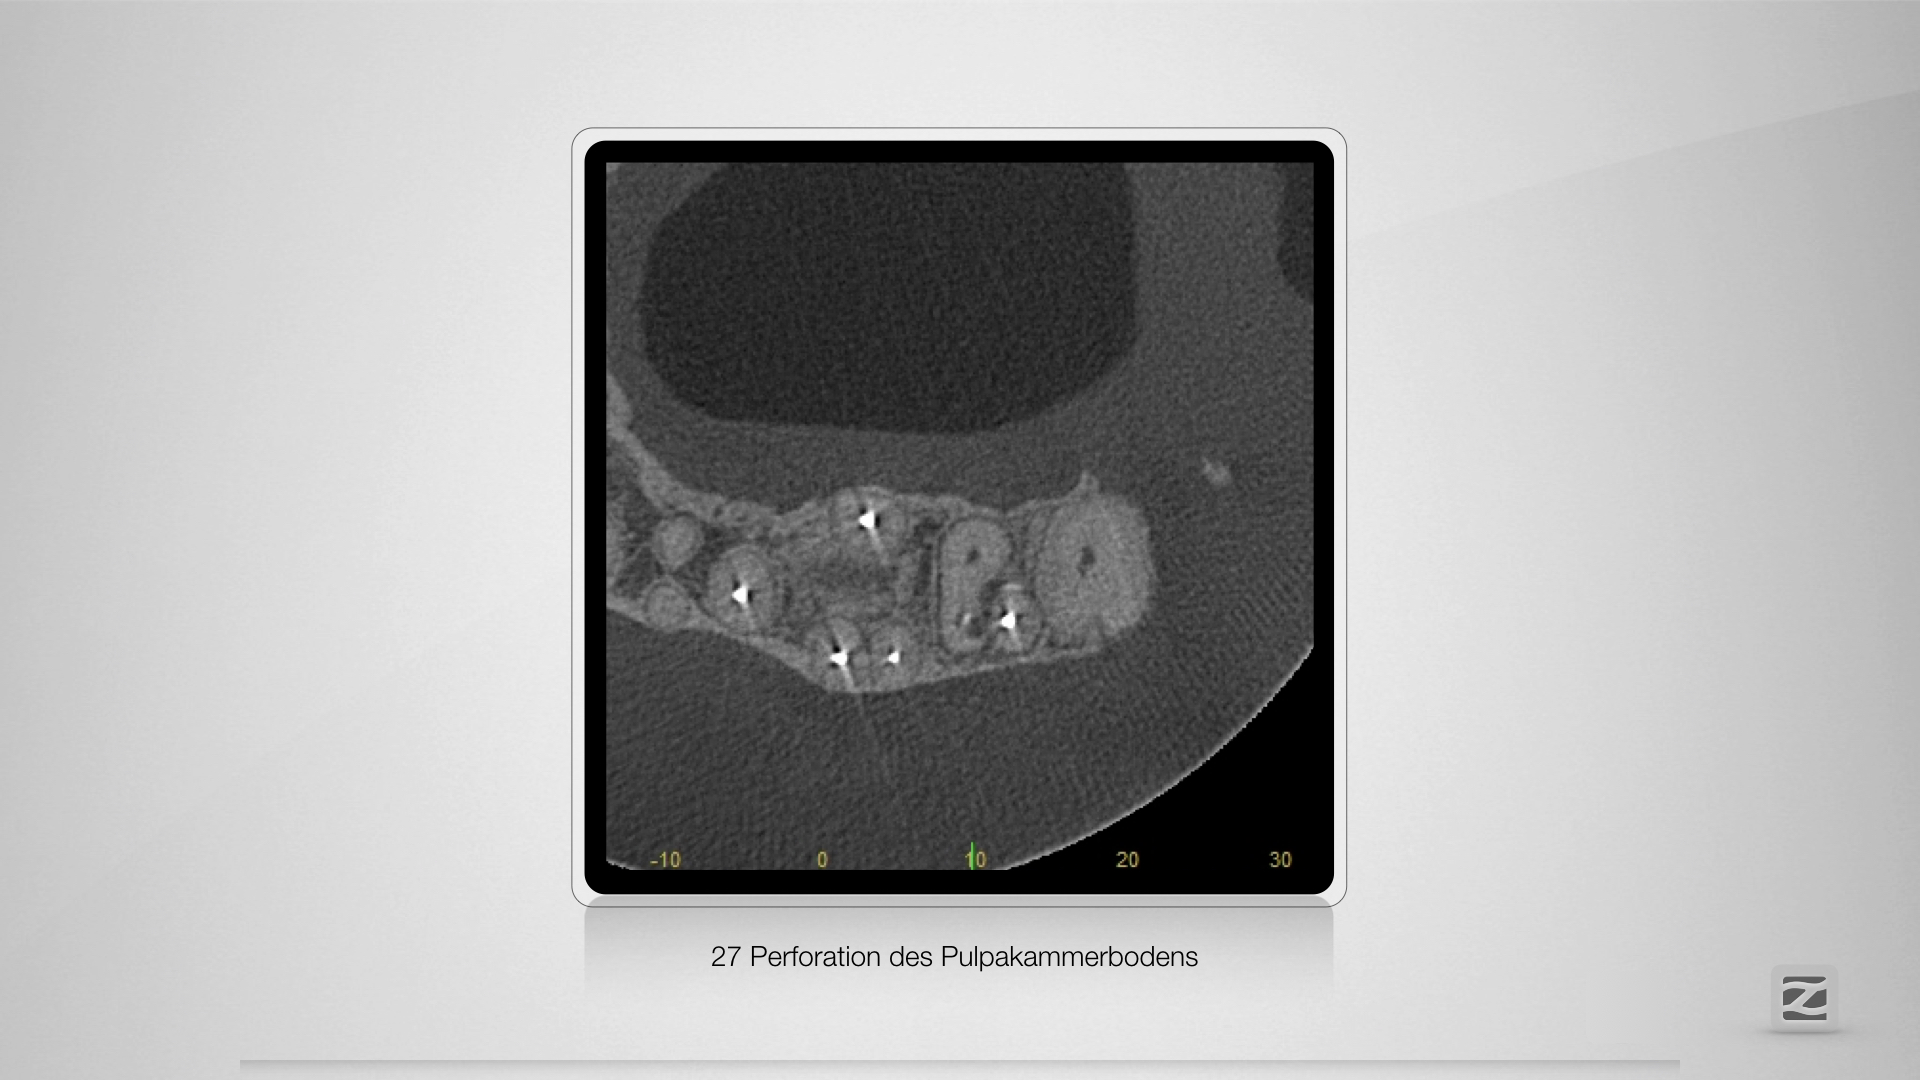

Fast getroffen ist auch vorbei!